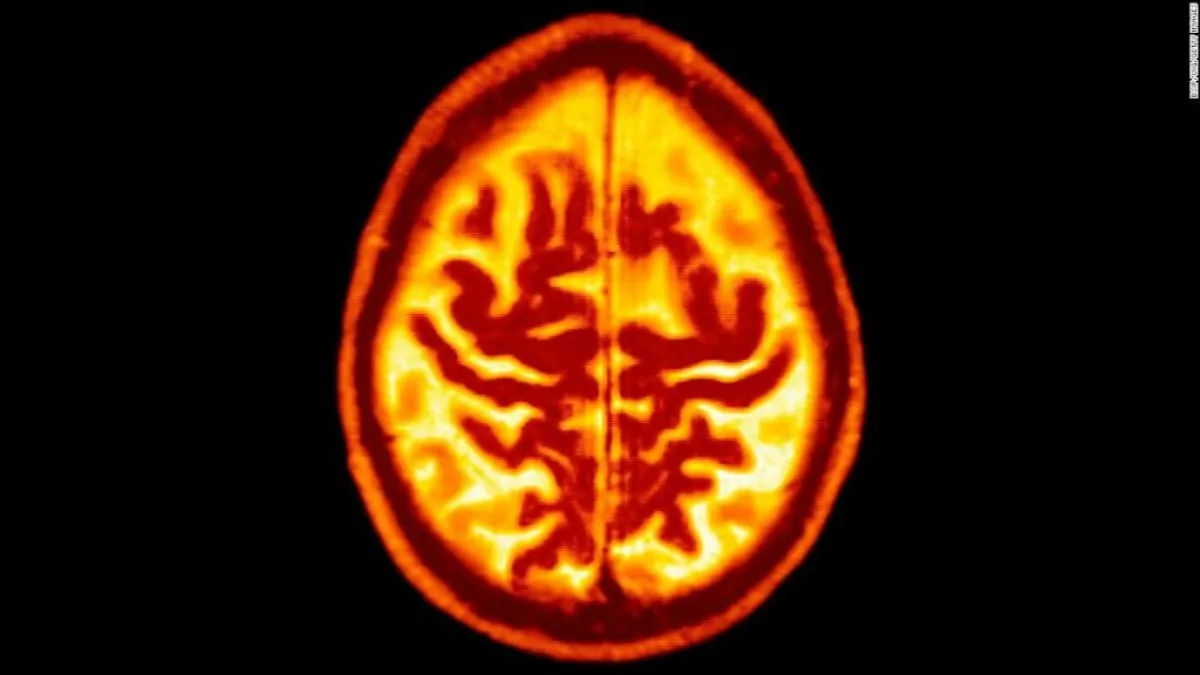

اكتشف علماء أن البكتيريا المسببة لنزيف اللثة، من الممكن انتقالها من الفم إلى الدماغ، وهو ما يزيد من خطر الإصابة بمرض الزهايمر.

وبحسب موقع "ساينس" العلمي، عثر العلماء على هذا النوع من البكتيريا المسببة لأمراض اللثة في أدمغة 51 مشاركاً من أصل 53 يعانون من مرض الزهايمر.

وكشفت الأبحاث أن الاهتمام بنظافة الفم والأسنان، يمكنه التقليل من خطر الإصابة بالخرف، حيث أن بكتيريا "Porphyromonas gingivalis"، والتي تعد السبب الرئيسي لأمراض اللثة، قادرة على الوصول إلى أدمغة الفئران بعد ستة أسابيع فقط من الإصابة بها.